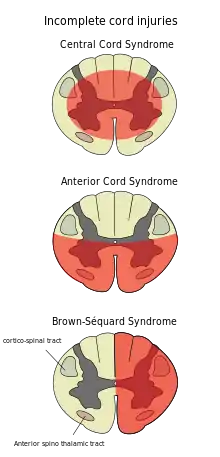

Central cord syndrome

Central cord syndrome, almost always resulting from damage to the cervical spinal cord, is characterized by weakness in the arms with relative sparing of the legs, and spared sensation in regions served by the sacral segments.[24] There is loss of sensation of pain, temperature, light touch, and pressure below the level of injury.[25] The spinal tracts that serve the arms are more affected due to their central location in the spinal cord, while the corticospinal fibers destined for the legs are spared due to their more external location.[25] The most common of the incomplete SCI syndromes, central cord syndrome usually results from neck hyperextension in older people with spinal stenosis. In younger people, it most commonly results from neck flexion.[26] The most common causes are falls and vehicle accidents; however other possible causes include spinal stenosis and impingement on the spinal cord by a tumor or intervertebral disc.[27]

Anterior spinal artery syndrome

Anterior spinal artery syndrome also known as anterior spinal cord syndrome, due to damage to the front portion of the spinal cord or reduction in the blood supply from the anterior spinal artery, can be caused by fractures or dislocations of vertebrae or herniated disks.[25] Below the level of injury, motor function, pain sensation, and temperature sensation are lost, while sense of touch and proprioception (sense of position in space) remain intact.[28][26] These differences are due to the relative locations of the spinal tracts responsible for each type of function.[25]

Brown-Séquard syndrome

Brown-Séquard syndrome occurs when the spinal cord is injured on one side much more than the other.[29] It is rare for the spinal cord to be truly hemisected (severed on one side), but partial lesions due to penetrating wounds (such as gunshot or knife wounds) or fractured vertebrae or tumors are common.[30] On the ipsilateral side of the injury (same side), the body loses motor function, proprioception, and senses of vibration and touch.[29] On the contralateral (opposite side) of the injury, there is a loss of pain and temperature sensations.[27][29]Spinothalamic tracts are in charge for pain and temperature sensation and because these tracts cross to the opposite side and above the spinal cord there is loss on the contralateral side.[31]